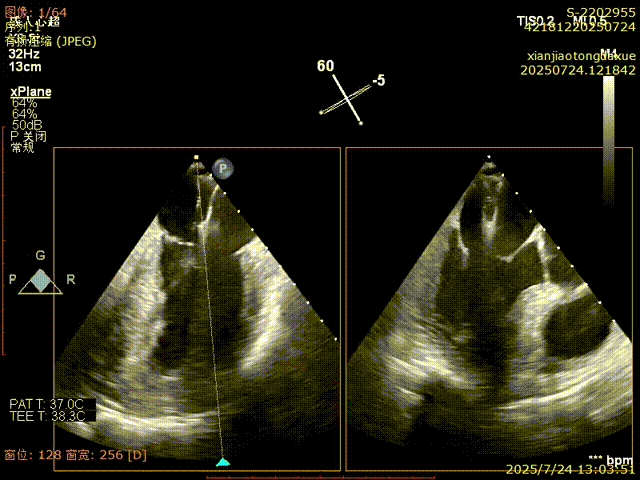

术前评估

影像评估提示病变位于二尖瓣三区交界,瓣膜结构复杂,患者低氧血症,无法耐受体外循环,传统外科修复风险高,微创TEER治疗成为优选方案。手术团队采用ValveClamp® II型夹进行精准定位与夹合。通过麻醉快速通道迅速、高效完成手术,术中经经食道超声(TEE)实时引导,夹子精准落点于三区交界,瓣叶抓取稳定,夹合线条自然,反流显著改善,术后即刻拔除气管 ,插管,术后无并发症,心功能恢复良好。

确认夹合位置及效果